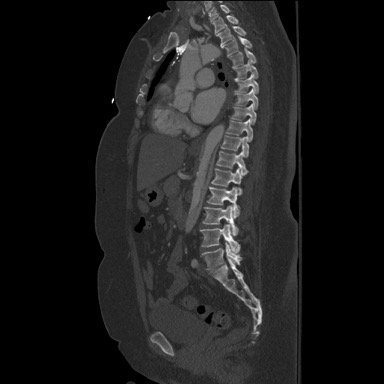

Because aortic dissection was suspected, the patient underwent urgent computed tomography (CT) angiogram of her chest, abdomen and pelvis that revealed her diagnosis.

The patient was found to have a Stanford type A dissection (see yellow arrow) with visible false lumen starting at aortic arch (see green circle). The dissection extended into the descending aorta (see blue circle) as shown by the false lumen (red highlighted area) visible on CT. The radiologist performed a reconstruction of the aorta, which showed that the left kidney was not being perfused, making the kidney not visible on the reconstruction.